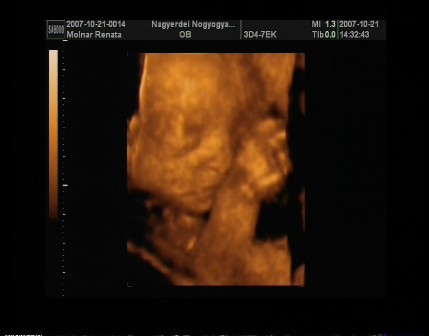

No jöttem beszámolni a pénteki UH-ról. A 4D-s UH végül 2D-s lett,mert a baba fekvése miatt semmi értelme nem lett volna a 4D-s UH-nak.Ugyanis a lelkem harántfekvésben van változatlanul,és a 15perces vizsgálat alatt végig háttal volt nekünk. Pedig nagyon meg lett macerálva és az istennek se akart megfordulni.Doki kb.5percig fel alá járkáltatott hátha felélénkül a drága,de nem...Kellett a bal oldalamra,és a jobb oldalamra is feküdnöm,ám ez sem segített. Finoman ütögette az érzékelőfejjel a hasamat és erre se akart megfordulni.Kis dacos... Ebéd után voltunk UH-on,doki kérdezte is hogy nem-e most ettem,mert baromi higgadt,nyugodt volt a baba,nem nagyon mozgott,és ugyebár meg se fordult.Erre mondtam,hogy igen...kiderült,hogy lehet hogy jobb lett volna ha éhgyomorra megyek,mert akkor élénkebb lett volna.Azt mondta a doki,hogy biztos most ő is jól van lakva,és pihen. A sok macerálás hatására azért háttal nekünk,de elkezdte a kezét,és a lábát emelgetni,meg picit a fejét is.Szegénykémet picit sajnálom,mert nagyon szűk még neki odabent ahogy elnéztem... Ő baromi gyorsan fejlődik,a vizsgálat napján én elvileg 15hetes1napos voltam,de a fejlettségi szintjét nézve a drágám,már akkor 15hetes5naposnak felelt meg. Látszik is,mert baromi pici helyen,teljesen kitölti az egész méhemet!Úgyhogy szerintem hamarosan nagyot fogok pocakosodni...

Picúrkáról nincs csak 1 képem,és azon se sokat látni belőle,mert csak a feje hátulját,és a jobb kezét,és öklét.Mást nem.De azt kristály tisztán. Egyébként 2D-s UH-on most láttam mindent először kristály tisztán.Láttam a kezeit,a gerincét(mint egy gyöngysor úgy nézett ki ),a bordáit,a két lábát,sőőt még a talpát is. És videófelvétel is készült róla.

A csodálatos értékei: a 2 fejkörfogat-->HC: 11.36, BPD: 3.34, pocikörfogata: 9.64(jó nagy már most... ), mellkas körfogata: 2.87, combcsontja: 1.70.